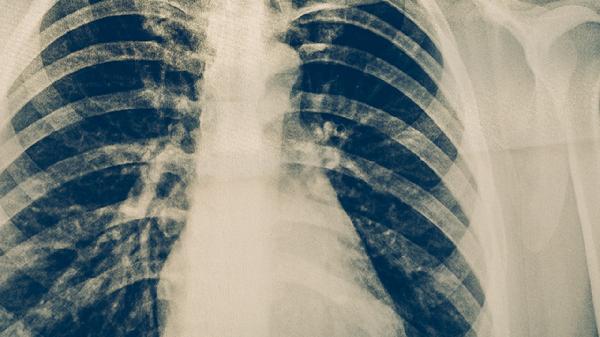

肺结核的早期症状有哪些?如何预防肺结核发生

肺结核这种疾病,发现的越早治疗效果越理想,当身体感染肺结核以后,会出现咳嗽、咳痰、咯血、发热、日渐疲劳、消瘦、盗汗等症,一旦身体上有什么症状跟这些相似,就要及时的就医。平时还要多锻炼身体、及时的接种疫苗,达到预防肺结核的目的。肺结核是最近几年,一种流行性的慢性传染疾病,这种疾病是很复杂的,根据病毒本